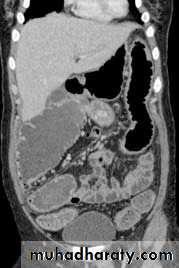

Hepatic secondaries , normal

Peritoneal deposit